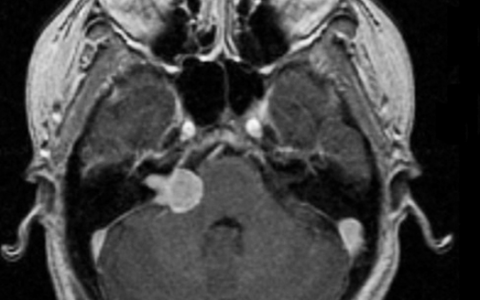

1、左侧图示(红色)患者术前核磁:右侧桥脑小脑角区见一类圆形占位性病变,边界清楚, T2WI高信号,其内信号欠均匀,增强扫描后病变呈明显强化,同侧桥脑小脑角池扩大,内听道扩大,四脑室轻微受压。